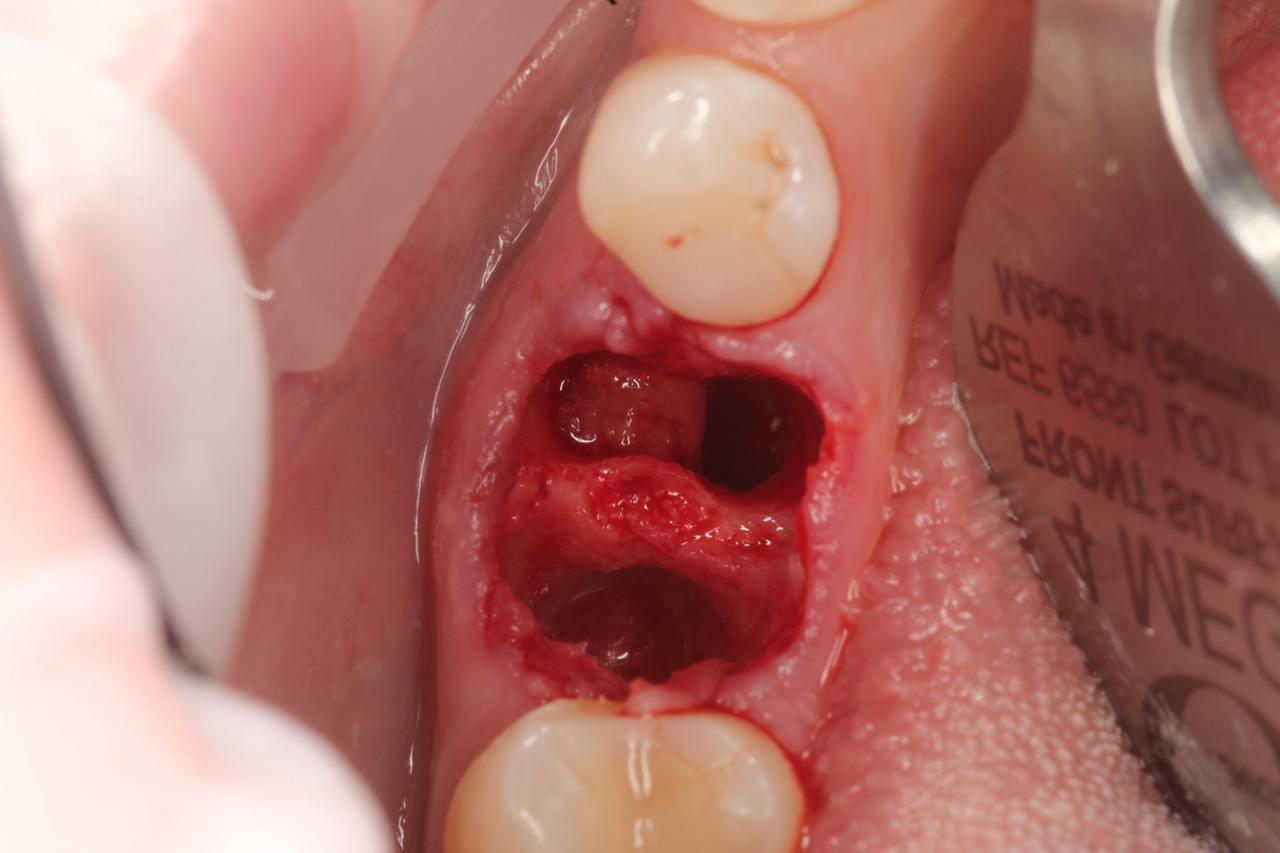

Перелечивание и ортопедическое восстановление в данном случае были невозможны — принято решение об удалении с одномоментной имплантацией. Как проходило лечение: 👇🏻

- атравматичное удаление зуба,

- тщательная подготовка ложа под имплантат